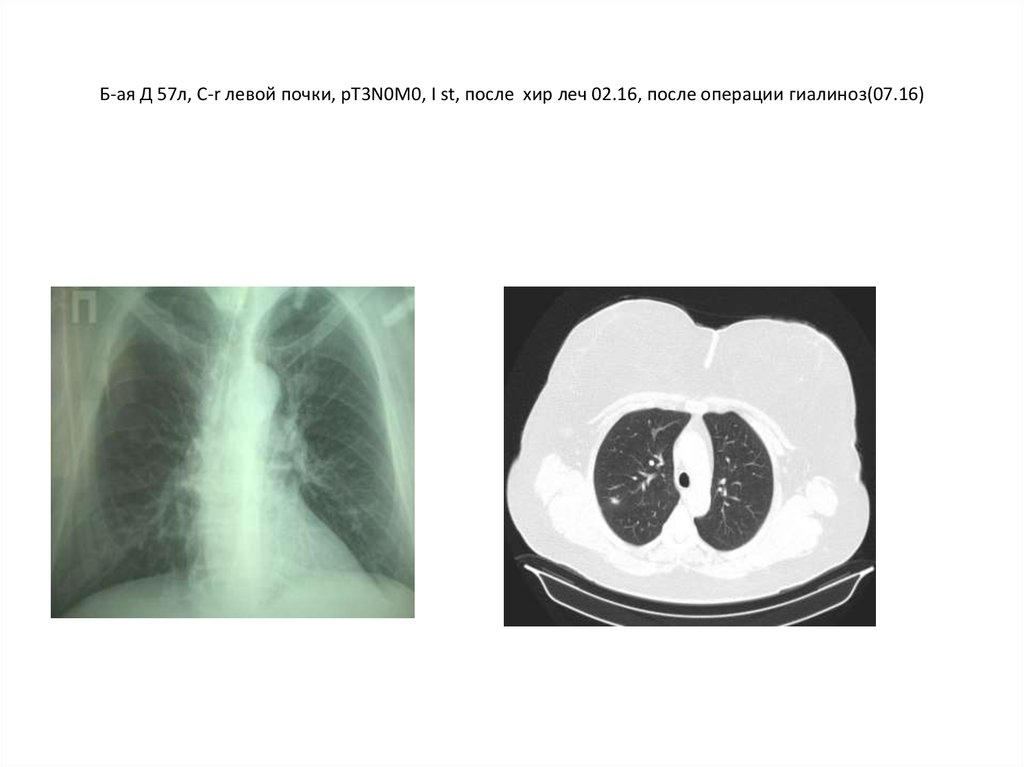

8. Б-ая Д 57л, C-r левой почки, рТ3N0M0, I st, после хир леч 02.16, после операции гиалиноз(07.16)